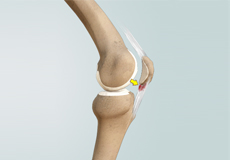

Patellar Instability

Any damage to the supporting ligaments may cause the patella to slip out of the groove either partially (subluxation) or completely (dislocation). This misalignment can damage the underlying soft structures such as muscles and ligaments that hold the kneecap in place.

Patellofemoral Instability

Patellofemoral instability means that the patella (kneecap) moves out of its normal pattern of alignment. This malalignment can damage the underlying soft structures such as muscles and ligaments that hold the knee in place.